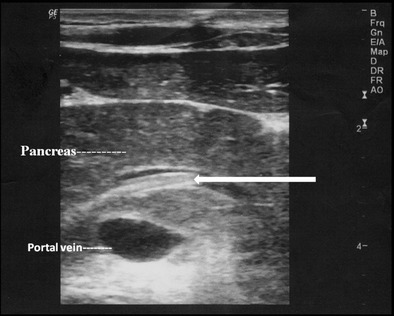

Pancreatic duct

Rarely, ascaris in the main pancreatic duct can present with pancreatitis. The main pancreatic duct may be dilated, with “triple line sign”, “strip sign” or an “inner tube sign” and occasional pancreatic oedema (Fig. 9).

Fig. 9.

A 15-year-old male presented with acute epigastric pain and elevated pancreatic enzymes. High resolution ultrasound using linear array transducer shows ascaris with triple line within in the dilated main pancreatic duct (long white arrow) with pancreatitis